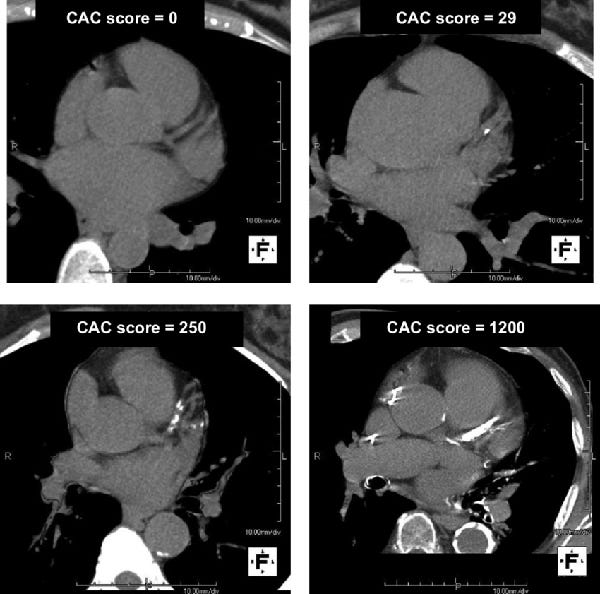

Image taken from a CT scan for coronary calcium scoring showing the Calcium Scan Of Heart Near Me Our advanced diagnostics ensure accurate assessments for proactive cardiovascular care. our cardiac imaging services include: a coronary artery calcium score is the measurement of calcium in the walls of the arteries that supply the heart muscle. It is measured by taking a special. — the aquilion one genesis allows our cardiologists to measure your calcium score. . Calcium Scan Of Heart Near Me.